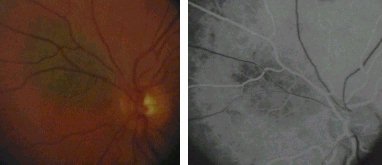

This is the right funuds of a patient with dry form of age-related macular degeneration. The macula shows areas of retinal pigment epithelium (RPE) atrophy.

The fluorescein angiography shows hyperfluorescence in the macula due to RPE window defect allowing choroidal fluorescein to show through brightly.